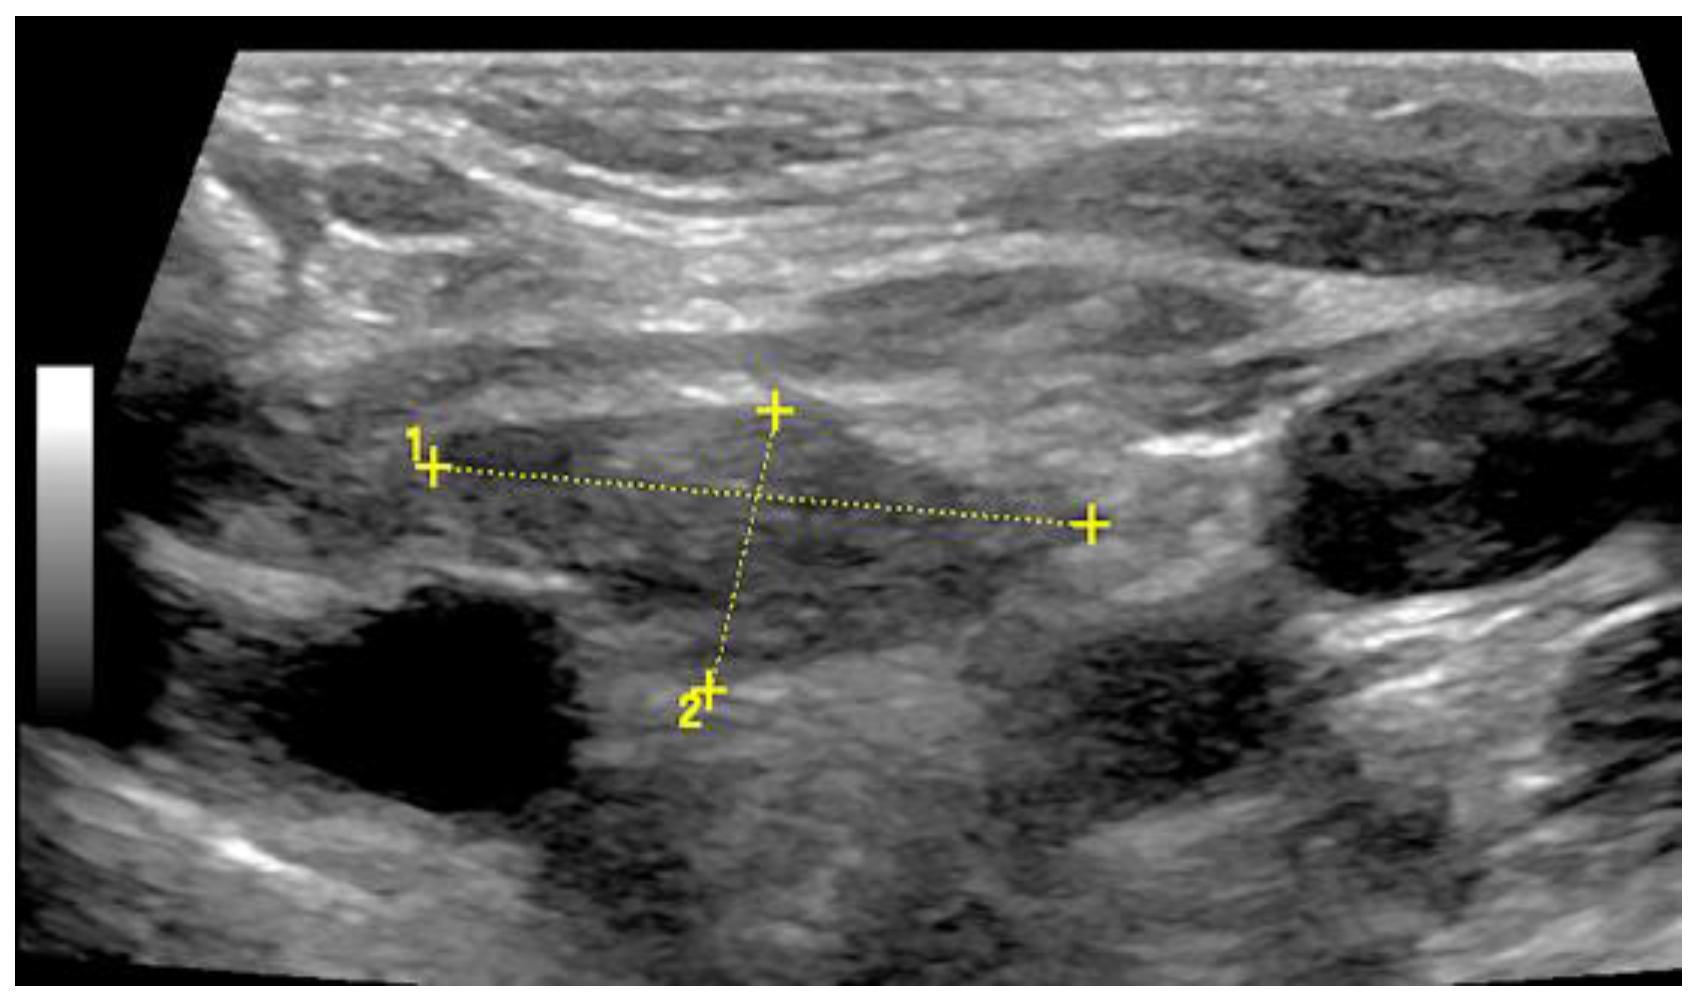

Reactive thymus enlargement (thymus rebound) can be observed after stressful situations (including surgery, burns, and chemotherapy) [31]. In childhood (2–8 years of age), thymic tissue is detectable in more than 90% of cases [33]. On US, the thymic tissue predominantly shows similar homogeneous echogenicity to that of the liver and spleen, with multiple hypoechoic strands. In individual cases, the thymic tissue shows an inhomogeneous echogenicity [34,35]. The hypoechoic strands appear as a “starry sky” on US and help to identify thymic tissue as such [34,35]. The characteristic US image is also helpful in identifying normal anatomic variants, such as cervical or retrocaval extensions of the thymus [34] (Figure 13).

Figure 13.

Illustration of a 2 cm × 1 cm sized thymus (thymoma) on B-mode US in an adult.